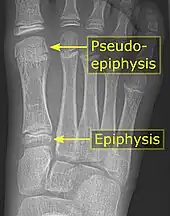

Pseudo-epiphysis

A pseudo-epiphysis is an epiphysis-looking end of a bone where an epiphysis is not normally located.[6] A pseudo-epiphysis is delineated by a transverse notch, looking similar to a growth plate.[6] However, these transverse notches lack the typical cell columns found in normal growth plates, and do not contribute significantly to longitudinal bone growth.[7] Pseudo-epiphyses are found at the distal end of the first metacarpal bone in 80% of the normal population, and at the proximal end of the second metacarpal in 60%.[6]